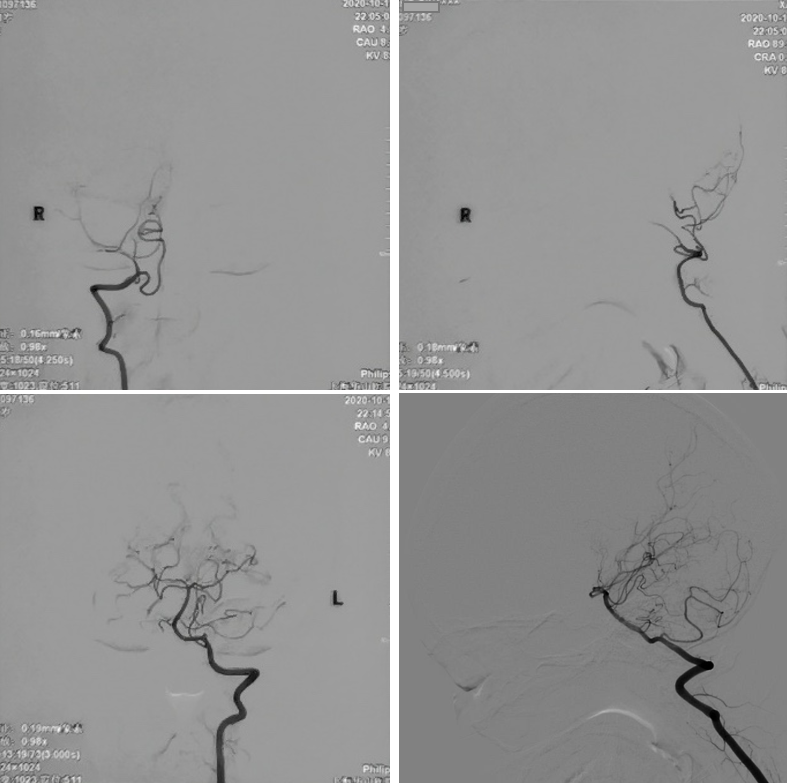

术中电生理未见明显异常,因此未进行进一步血流重建处理。